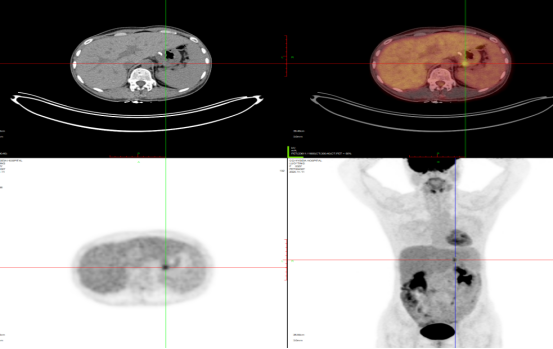

淋巴瘤治疗后2021-2-25 2021-7-24